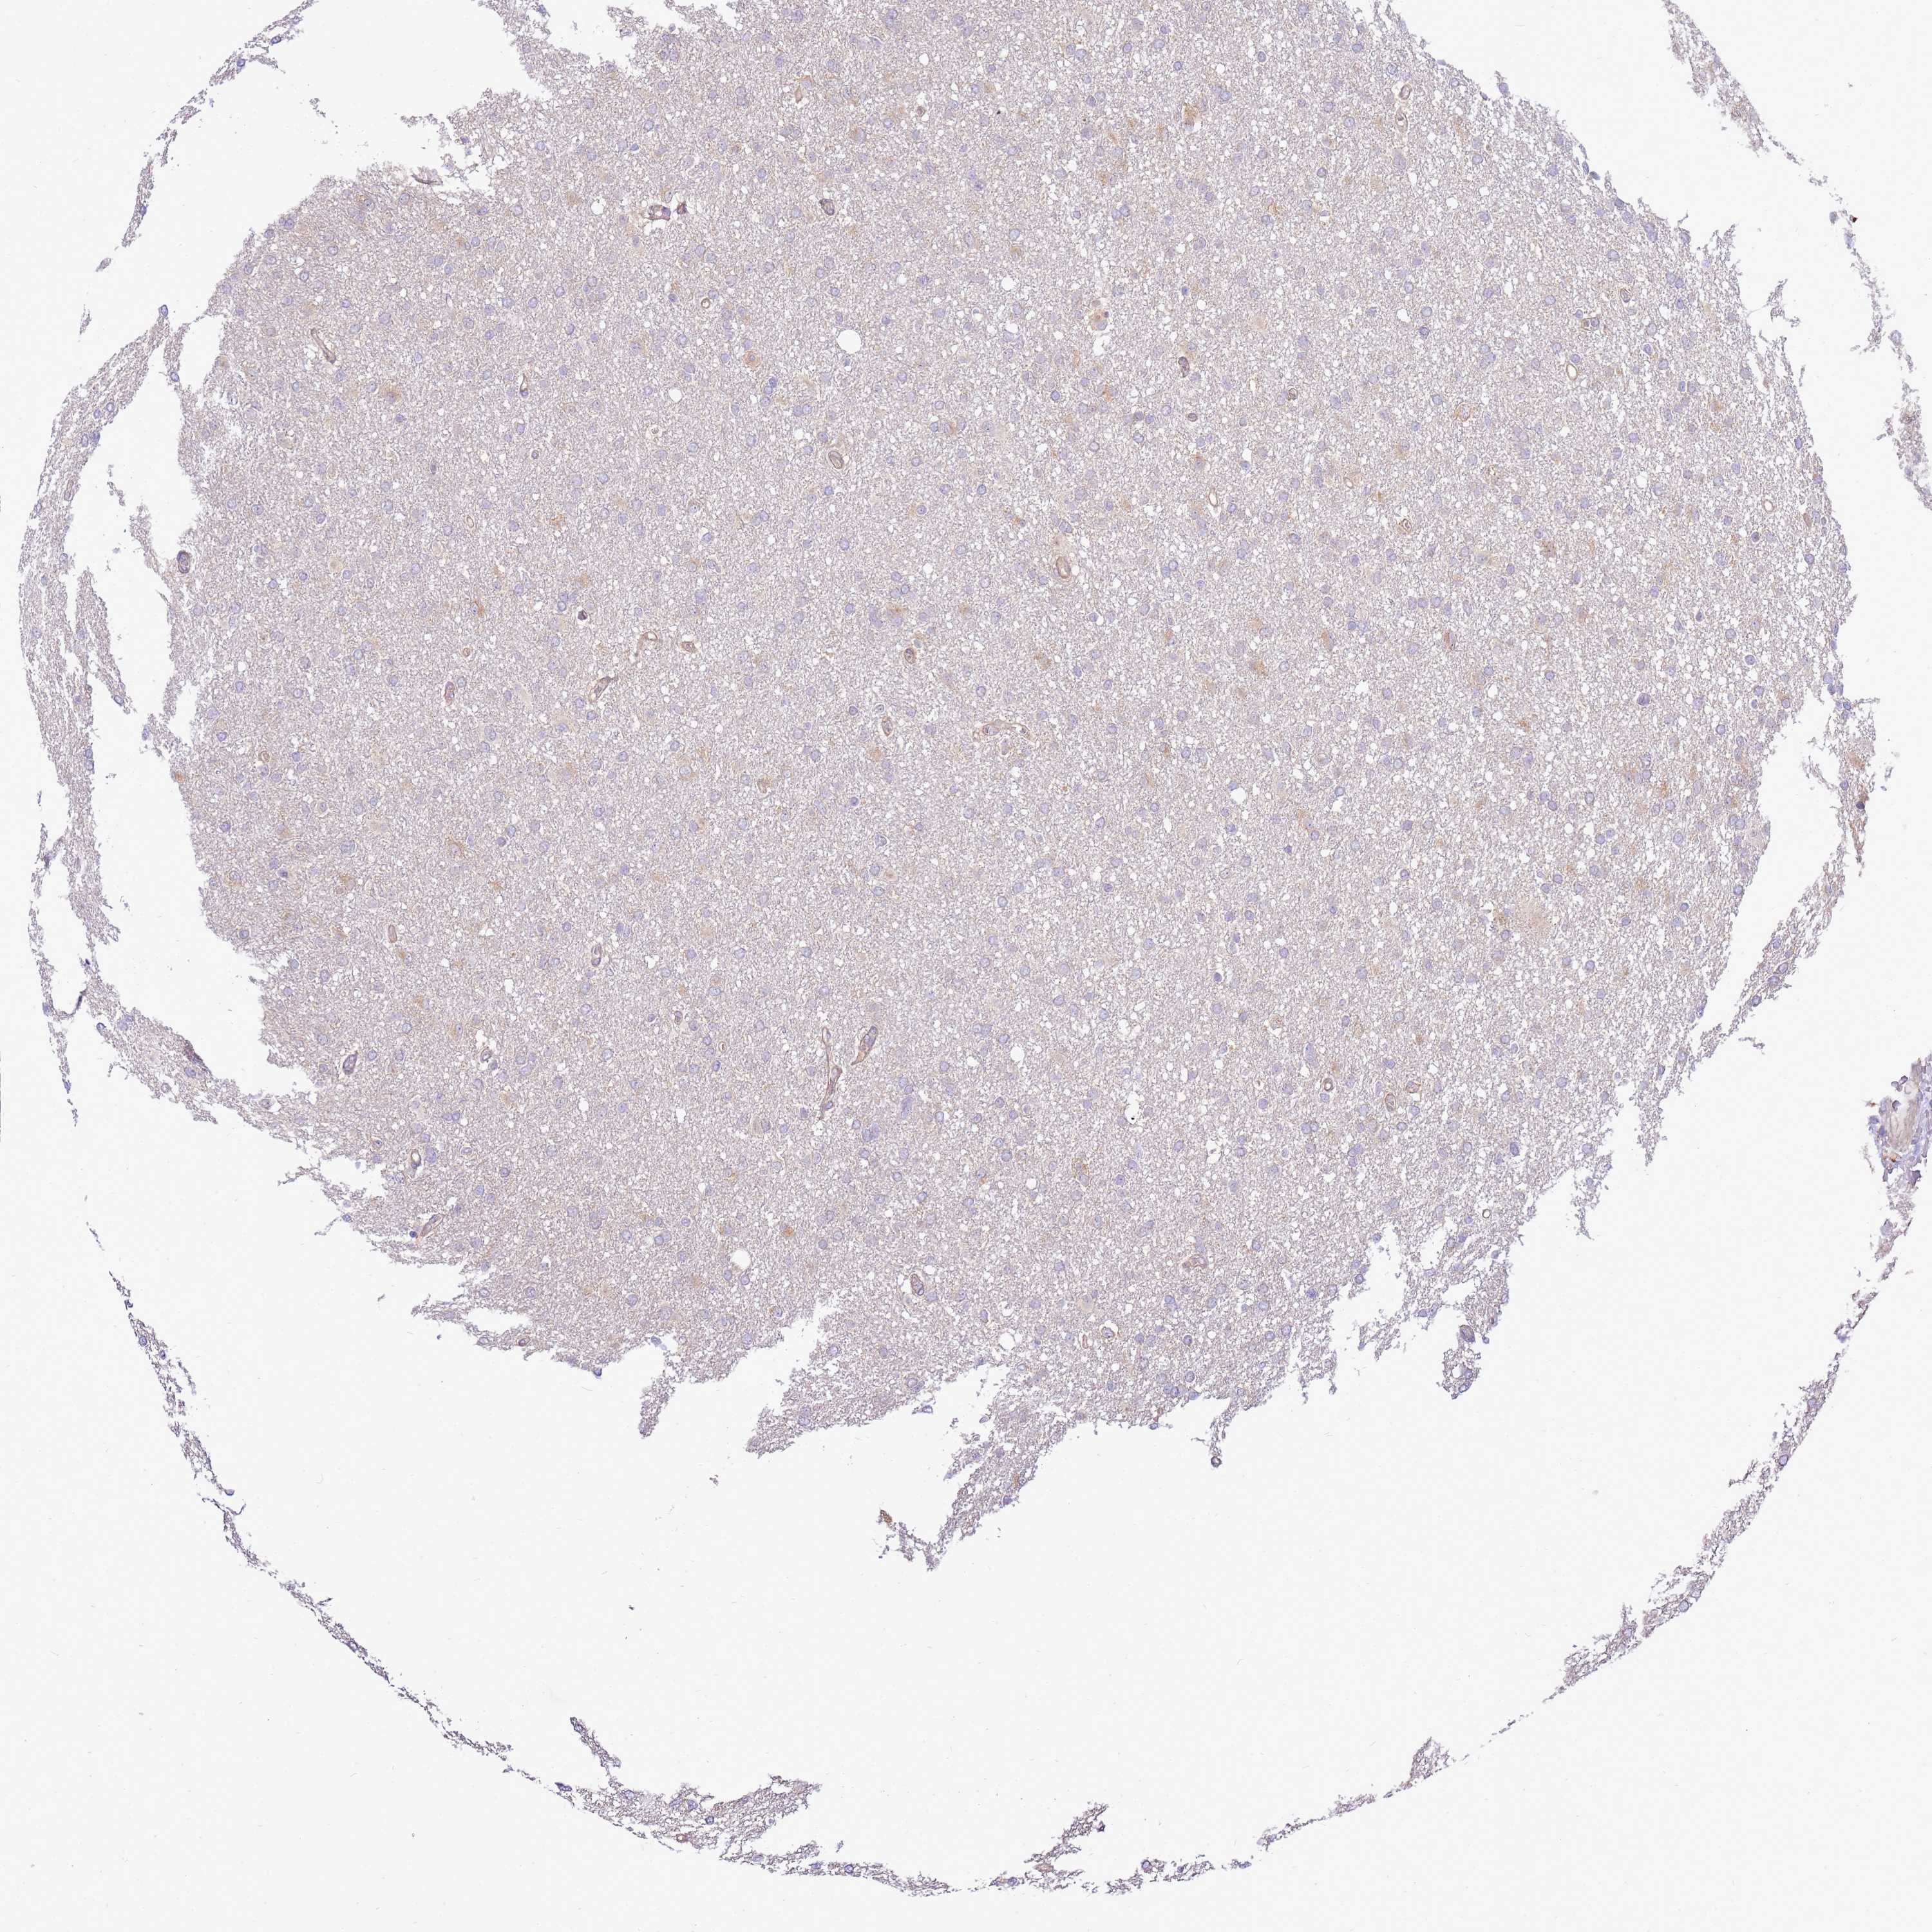

GLIOMA - Protein expressioni

A mouse-over function shows sample information and annotation data. Click on an image to view it in a full screen mode. Samples can be filtered based on level of antibody staining by selecting one or several of the following categories: high, medium, low and not detected. The assay and annotation is described here.

Note that samples used for immunohistochemistry by the Human Protein Atlas do not correspond to samples in the TCGA dataset.

Antibody stainingi

Antibody staining in the annotated cell types in the current human tissue is reported as not detected, low, medium, or high, based on conventional immunohistochemistry profiling in selected tissues. This score is based on the combination of the staining intensity and fraction of stained cells.

Each image is clickable and will lead to virtual microscopy that enables deeper exploration of all samples and also displays staining intensity scores, fraction scores and subcellular localization as well as patient and tissue information for each sample.

Antibody HPA047386

Staining

High

Medium

Low

Not detected

Intensity

Strong

Moderate

Weak

Negative

Quantity

>75%

75%-25%

<25%

None

Location

Nuclear

Cytoplasmic/membranous

Cytoplasmic/membranous,nuclear

Glioma, malignant, High grade

Glioma, malignant, Low grade